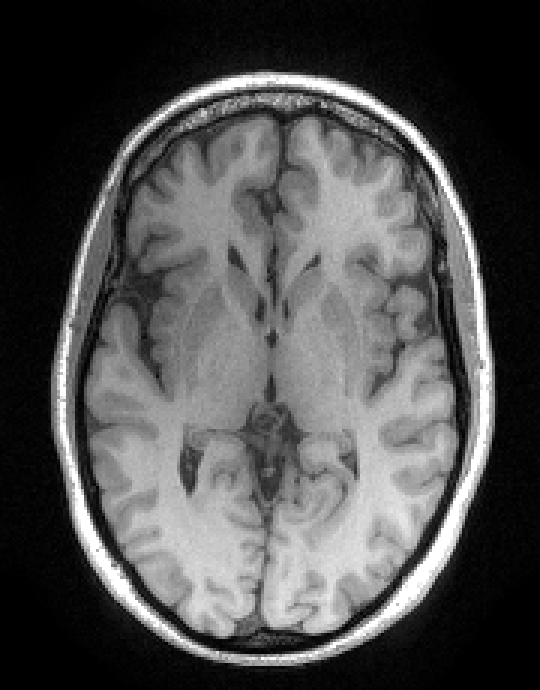

In the first set of evaluations, we considered the reconstruction of an MR image from -undersampled k-space data. The gold-standard magnitude and phase images, which were obtained from a real fully-sampled in vivo T1-weighted MRI acquisition with in-plane matrix size, are shown in Fig. 1. This figure also shows the k-space sampling mask (corresponding to undersampling) that we used to simulate an accelerated acquisition.

For this simulation, the original fully-sampled k-space data (originally measured with 32 channels) was coil-compressed down to 8 virtual channels to reduce computational complexity, and was then retrospectively undersampled using the aforementioned k-space sampling mask. For reconstruction, the matrix was chosen according to the standard SENSE model [41], with sensitivity maps estimated using ESPIRiT [42]. The magnitude regularization took the form of an penalty as given by Eq. (40), where, following Ref. [8], the sparsifying transform was chosen to be the unitary Daubechies-4 wavelet transform. The phase regularization took the form of a Huber-function penalty as given by Eq. (41), where the Huber parameter was chosen to be a small number (i.e., ) in order to approximate the -norm. Following Ref. [8], the transform we used for phase regularization was also a unitary Daubechies-4 wavelet transform. All three algorithms were initialized by applying SENSE-based coil-combination to the multi-channel images obtained by zero-filling the unmeasured data.